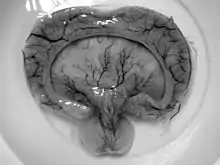

Gross pathology specimen from a case of alobar holoprosencephaly

• Alobar

• Most severe form includes formation of synophthalmia (a single central eye), proboscis, and severe impairment.[3]